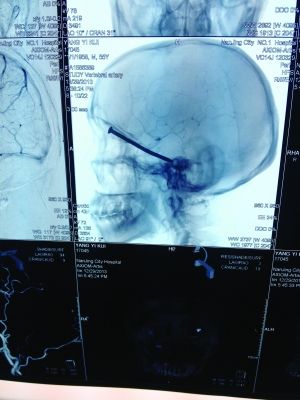

CT投影

CT投影結(jié)果,把大家嚇了一跳:楊先生腦子里居然有一根長釘,從眼眶一直“伸”到了接近后腦勺的位置!鐵釘細長略帶彎曲,長達8厘米。根據(jù)推測,鐵釘應(yīng)該是從上眼眶的縫隙中飛入,一直插進腦顱中,末端還有一個小小凸出的釘帽。